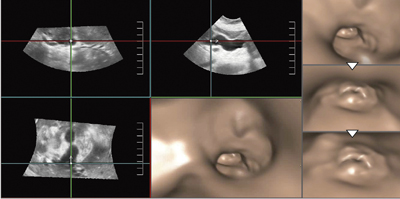

図1は,深部静脈血栓症による表在静脈の怒張の画像だが,Bモードの2D画像では,一見してつながりが弱く見える。超音波画像に熟練していれば連続した管腔だとわかるが,経験の少ない医師や患者には2D画像からつながりを認識することは難しい。Fly Thruの3D画像であれば,複雑な走行であってもつながりが容易に把握できる。また,総胆管結石などでも,2D画像の説明では,患者の理解を得るのは大変だが,Fly Thruでは動的に胆管と結石の大きさが提示でき,視覚的に理解が得られやすいと考えられる。

図1 深部静脈血栓症による表在静脈の怒張のFly Thru画像

2Dではイメージしにくい“つながり”を容易に把握できる。(動画)